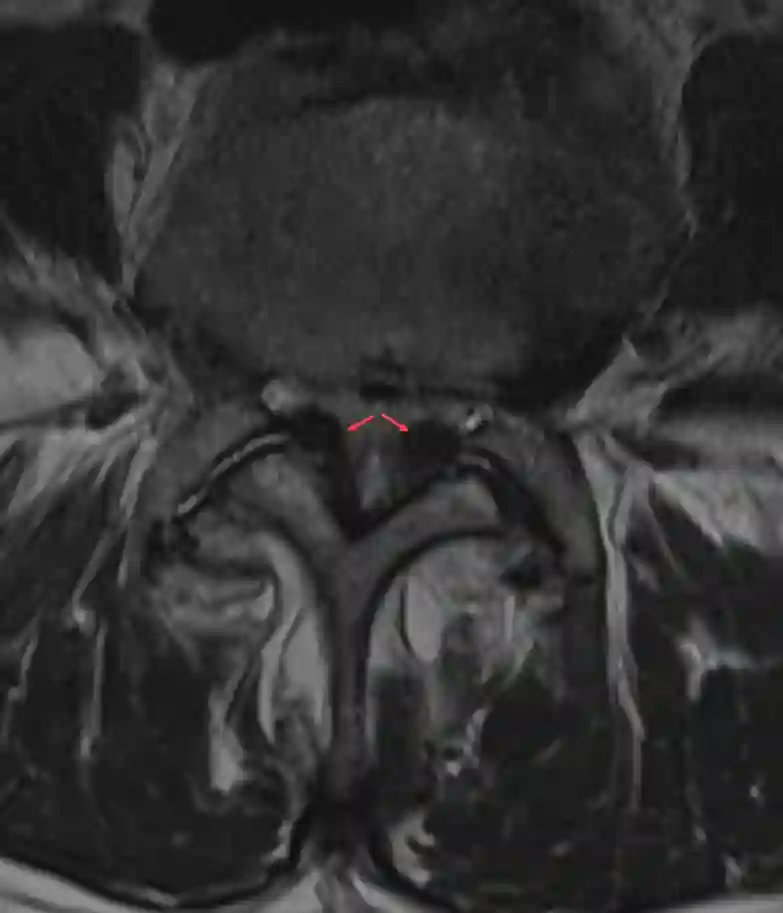

Absolute Spinalkanalstenose durch Ligamentum flavum Hypertrophie

Darstellung einer absoluten Spinalkanalstenose im axialen T2 gewichteten MRI auf Grund einer Hypertrophie des Ligamentum flavums.